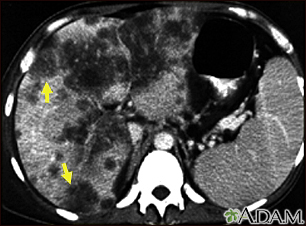

Hepatocellular cancer - CT scan